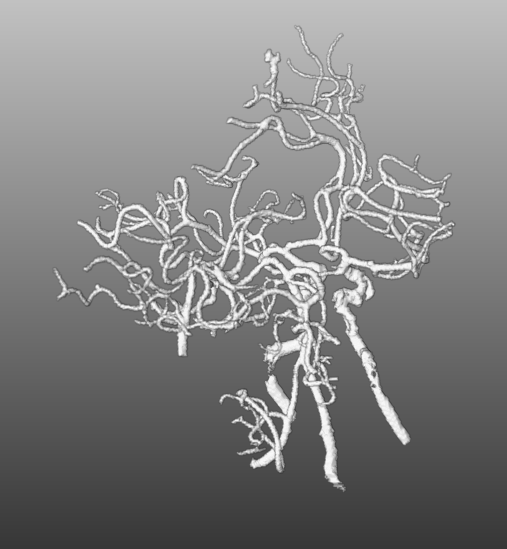

For the interactive part of our work, the segmentation must be modeles as geometric representation e.g. as graph of centerlines and lumen radii. First, as tiny gaps may occur in the segmentation, closing is applied, followed by the Distance-Transform-Skeletonization algorithm (short, DTF-Skeletonization) (Selle, 2000), which returns not only the skeleton itself but also a surface model of the vascular structures. Examples trees are shown in Fig. 3, Fig. 5, Fig. 5 and Fig. 6(a). Once the model is available, the information required of the interactive masking (geodesic distances) is computed in Fig. 2(k). As the processing consists primarily of searching pathways on the skeleton representation, the step is called “Graph Search”. In Sec. 4.2.1 we present the generic concept of pathway searches on vessel trees, from which it is possible to derive applications. Exemplarily, we present two applications consequently following from the formal concept introduction, namely the interactive path search in Sec. 4.2.3 and the interactive suppression of veins in Sec. 4.2.2.

Figure 3: The surface model of the vessel tree of two patients demonstrating the vein suppression feature on different rendering distances. The upper row is an example of a patient with no LVO present. Contrary to the lower row, where the patient suffers an LVO on the left MCA branch. The expansion on the far right shows the full vessel tree including all veins. Relevant structures close to the Circle of Willis are visually obstructed.

4.2.2 Vein Suppression

In some cases, for instance if large contrast boluses were injected, veins like the sinus sagittalis may disturb the visual impression. The second search node property enables an easy way of displaying only relevant parts by placing the root node into the Circle of Willis and visualizing only nodes and their paths accessible within a certain geodesic distance. Fig. 3 shows two trees on different geodesic distances. The lower tree is from a patient who suffers an LVO on the left MCA branch, while the top one is LVO negative, showing no noticeable defects. As displayed, veins and more distant vessels may conceal stroke-relevant parts in their full representation on the right end and disappear towards the left side while the distance is decreased.